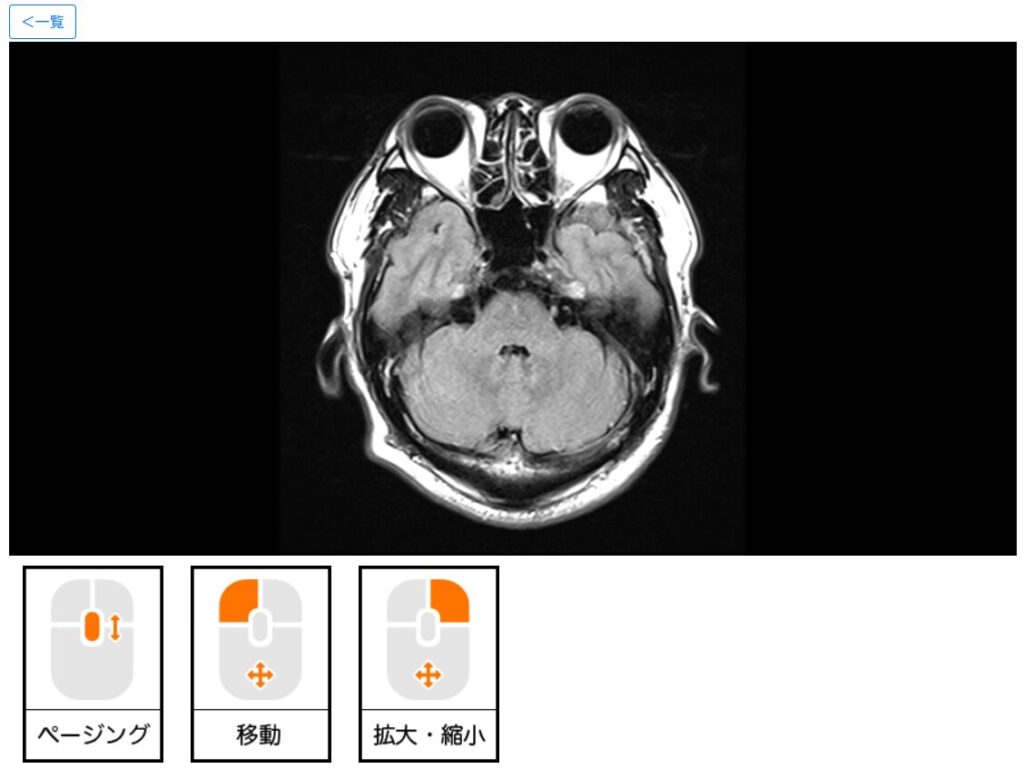

この[すべての撮影画像を見る]ボタンから、脳の断面図を連続的に確認できます。マウスのスクロールホイールでぐりぐりと変化します。